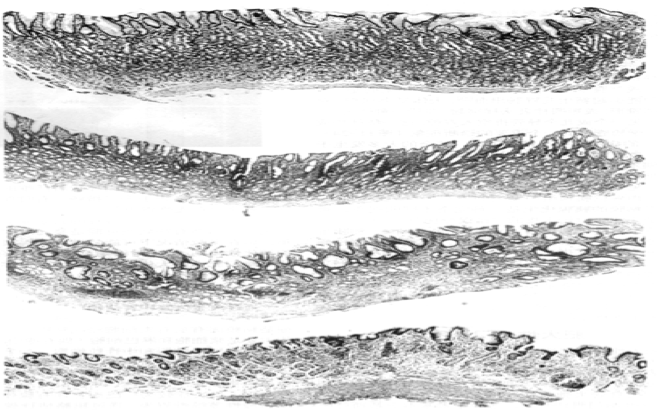

2.慢性萎缩性胃炎(chronic atrophic gastritis) 呈逐年增多趋势,与胃粘膜活检增多相关。胃窦部最常见。

(1)胃镜下见:①粘膜变薄,皱壁变平或消失,表面细颗粒状;②正常桔红色消失、变浅,呈灰白或灰黄;③粘膜下血管清晰可见,伴渗出、糜烂。

(2)镜下呈:

① 粘膜全层淋巴细胞、浆细胞浸润,可伴淋巴滤泡形成;

② 胃小凹变浅,粘膜固有层腺体萎缩、稀疏,腺体变小并见散在腺体小囊状扩张;

③ 肠上皮化生(肠化)和假幽门腺化生。胃粘膜上皮被肠粘膜上皮取代称肠化,可再分为小肠性化生(完全性化生)和结肠性化生(不完全性化生)。小肠性化生见吸收细胞及纹状缘、杯状细胞和Paneth细胞,分泌唾液酸粘液,组织化学示奥辛蓝(Alcian blue)染色阳性。结肠性化生无Paneth细胞和纹状缘,分泌硫酸粘液,高铁二胺染色阳性。通常认为结肠性化生与胃癌关系密切。假幽门腺化生指胃底和胃体部的壁细胞和主细胞消失,由分泌粘液的细胞取代后似幽门腺而称之;

④急性活动期可见多量嗜中性粒细胞浸润和糜烂。

(3)慢性萎缩性胃炎分级

依据腺体萎缩的程度将萎缩性胃炎分三级:轻度指胃粘膜厚度无明显变薄,仅个别或灶性腺体萎缩、减少,不超过原有腺体数量的1/3,重度指胃粘膜厚度明显变薄,腺体萎缩、减少的数量超过2/3,介于二者之间的为中度。